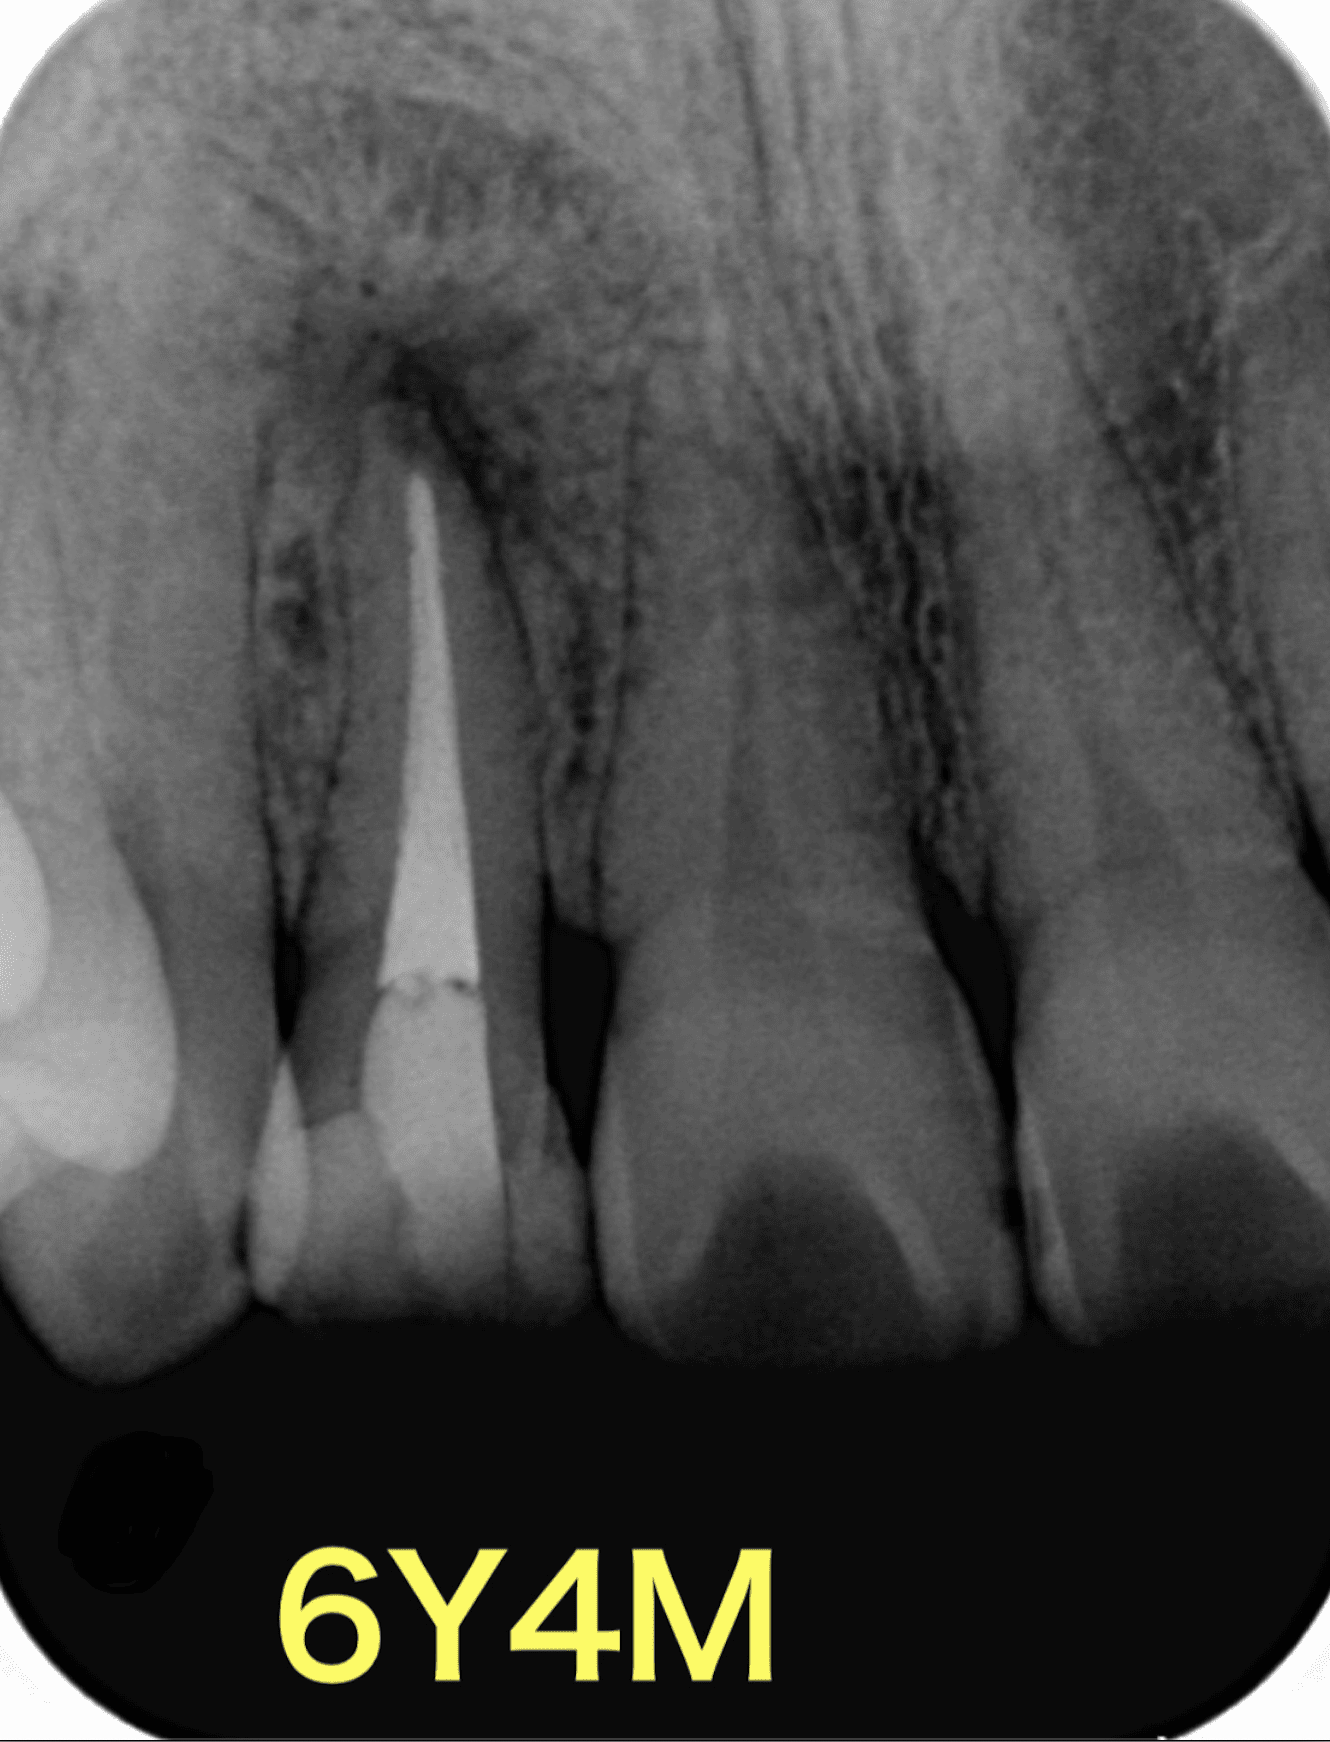

根管治療はやはり大事である

ということを示す一例。

そして、症状がないのであれば経過を追う!